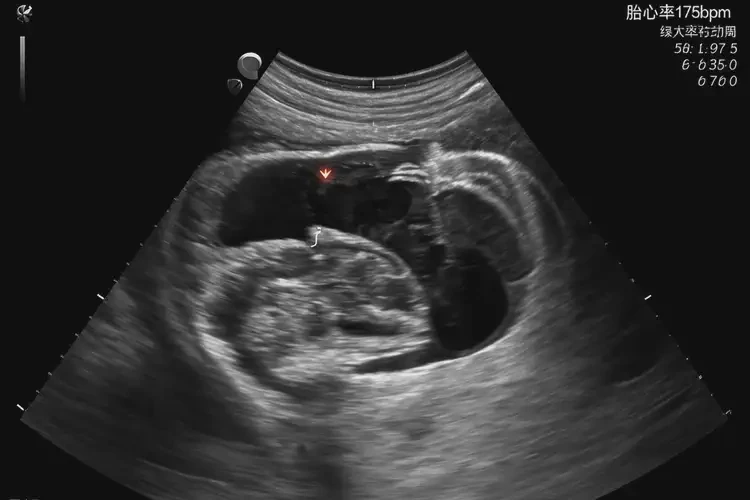

孕9周1天胎心175正常嗎

胎心率175次/分鐘在孕9周1天屬于正常范圍。

胎心率是指胎兒心臟每分鐘跳動(dòng)的次數(shù),是評(píng)估胎兒健康狀況的重要指標(biāo)之一。在孕早期,胎心率通常較快,隨著孕周的增加,胎心率會(huì)逐漸減慢并趨于穩(wěn)定。根據(jù)醫(yī)學(xué)研究和臨床經(jīng)驗(yàn),孕9周左右的胎心率正常范圍為140-180次/分鐘。胎心率175次/分鐘在孕9周1天是正常的。

孕9周1天胎心175正常嗎(圖1)